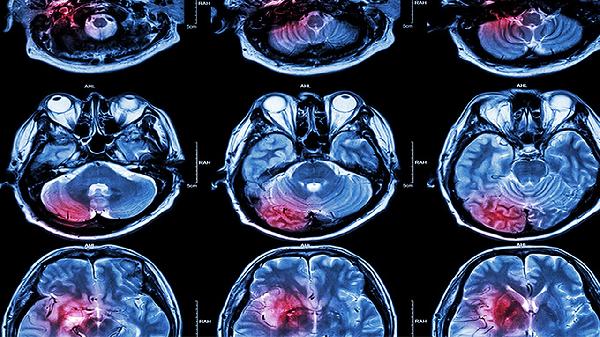

中老年人因脑血管硬化导致的认知功能下降,可在医生指导下配合使用脑灵素片。该药通过增加脑血流量和氧利用率改善记忆力。但对于阿尔茨海默病等退行性疾病,需联合专业治疗方案,不可依赖单一药物。